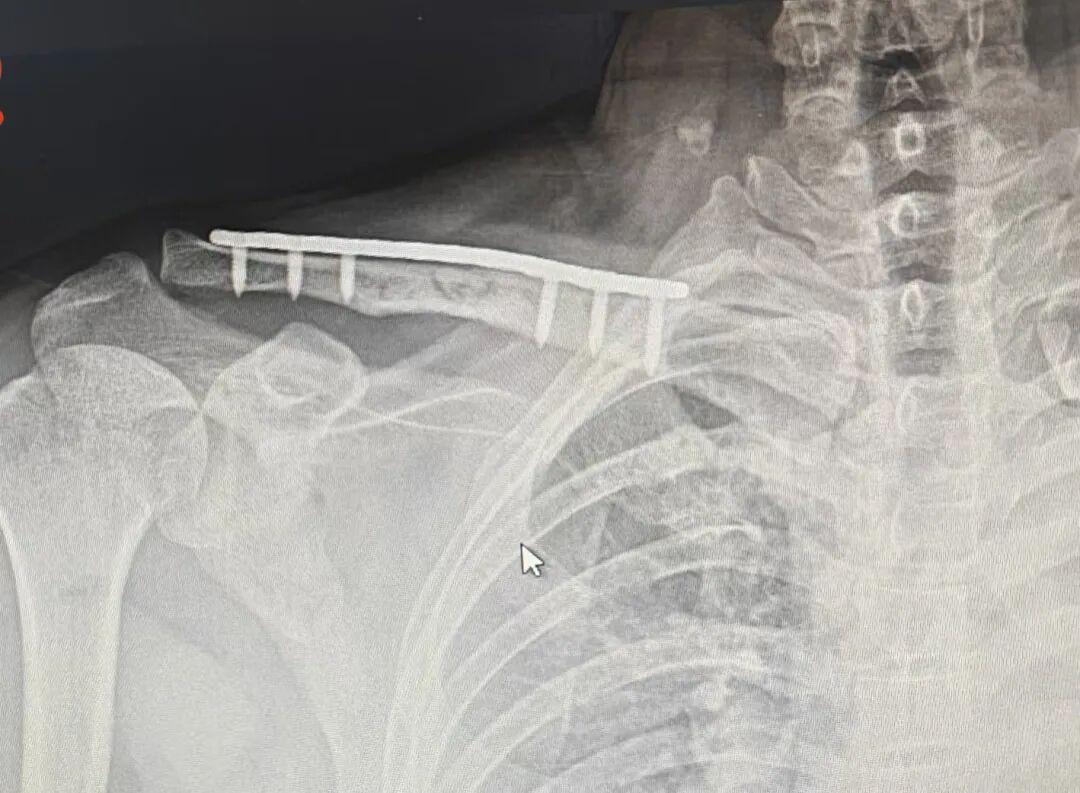

青年男性,锁骨粉碎性骨折

从片子上看

钢板够长,钉子打的也挺好

骨折复位还是不错的

并且没有游离螺钉,没有钢丝